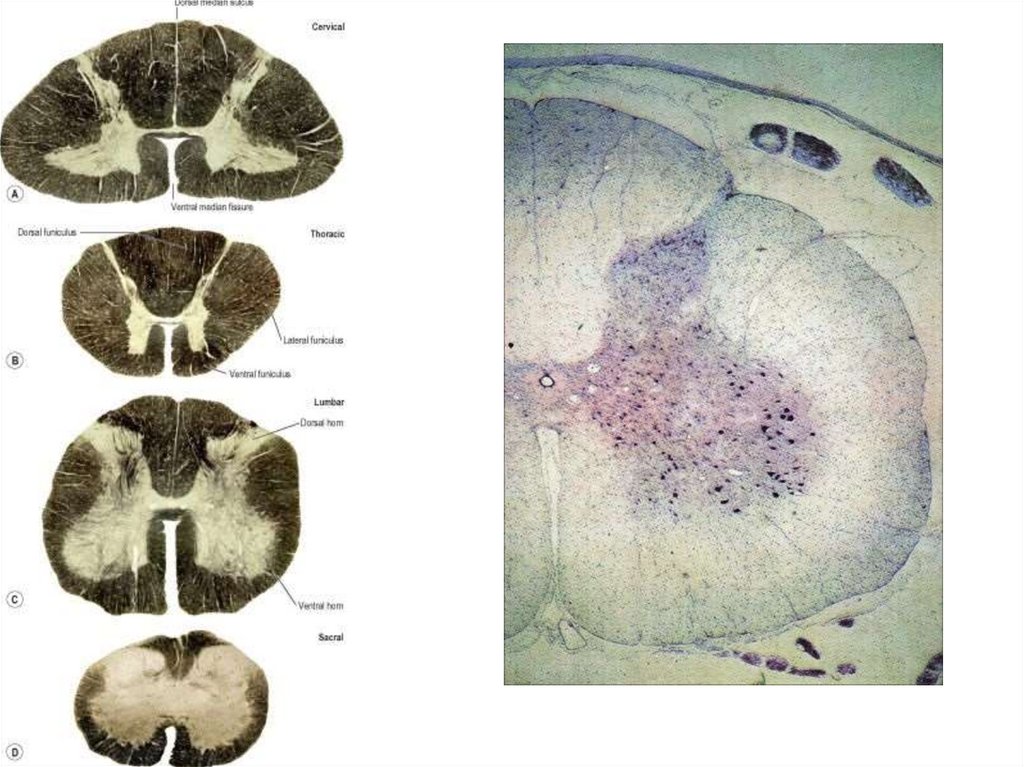

• Спинной мозг состоит из двух симметричных

половин, разделенных спереди глубокой

срединной щелью (fissura mediana), а сзади срединной бороздой (sulcus medianus).

• На правой и левой половинах имеются

передняя и задняя боковые борозды (sulci

laterales anterior et posterior), в которых

соответственно располагаются двигательные

и чувствительные нервные корешки.

• Борозды спинного мозга и срединная щель

ограничивают три канатика белого вещества,

расположенных на поверхности серого

вещества. Канатики образованы нервными

волокнами, которые по функциональным

свойствам группируются, формируя так

называемые проводящие пути.

• Серое вещество спинного мозга (substantia grisea

medullae spinalis) занимает центральное положение в

спинном мозге, проявляясь на поперечном разрезе в

виде буквы "Н«, вид «бабочки». Оно состоит из

нервных мультиполярных клеток, безмиелиновых

волокон и нейроглии.

• Нервные клетки формируют ядра, которые на

протяжении спинного мозга сливаются в передние,

боковые и задние столбы серого вещества (columnae

anterior, lateralis et posterior).

• Эти столбы посредине соединены передней и задней

серыми спайками (commisurae griseae anterior et

posterior), разделенными центральным

спинномозговым каналом, представляющим

редуцированный канал эмбриональной нервной

трубки.